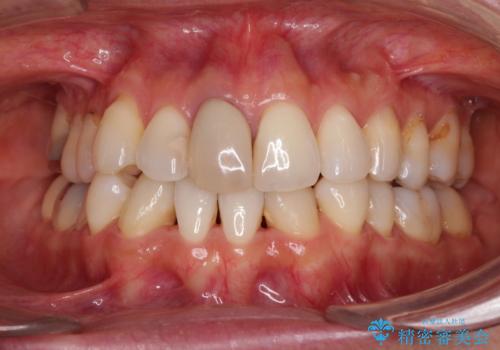

失活により変色した前歯 オールセラミッククラウンによる審美歯科治療

- 前歯の変色を気にして来院された患者様です。

ラミネートベニアによる治療を以前受けていたものの、神経組織が失活して以降、徐々に変色してきたとのことでした。

オールセラミッククラウンにて補綴治療を行うこととしました。

周りの歯と調和した、自然な仕上がりとなりました。